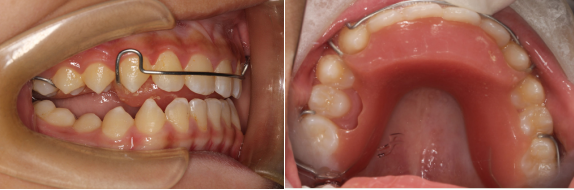

对于高角的II类下颌后缩问题,我们可以考虑使用Twin-Block功能矫治器,因为高角下巴后缩矫正策略是压低后牙,而Twin-Block功能矫治器恰好会带来后牙的压低。

Twin-Block矫治器的结构分为上下两个咬合板,那么我们在制作Twin-Block的时候,给患者采蜡颌记录,通常采4-5毫米的蜡颌记录,为什么是这个高度呢?

临床注意:Twin-Block 矫治器的上、下颌部分是分开的,孩子要能自由地前伸下颌,使下颌颌垫位于上颌颌垫前方。如果不能,一般是因为颌垫过高或前伸量过大,可通过调磨来解决。必要时,重新取咬合记录,减小后牙开合和下颌前移量。